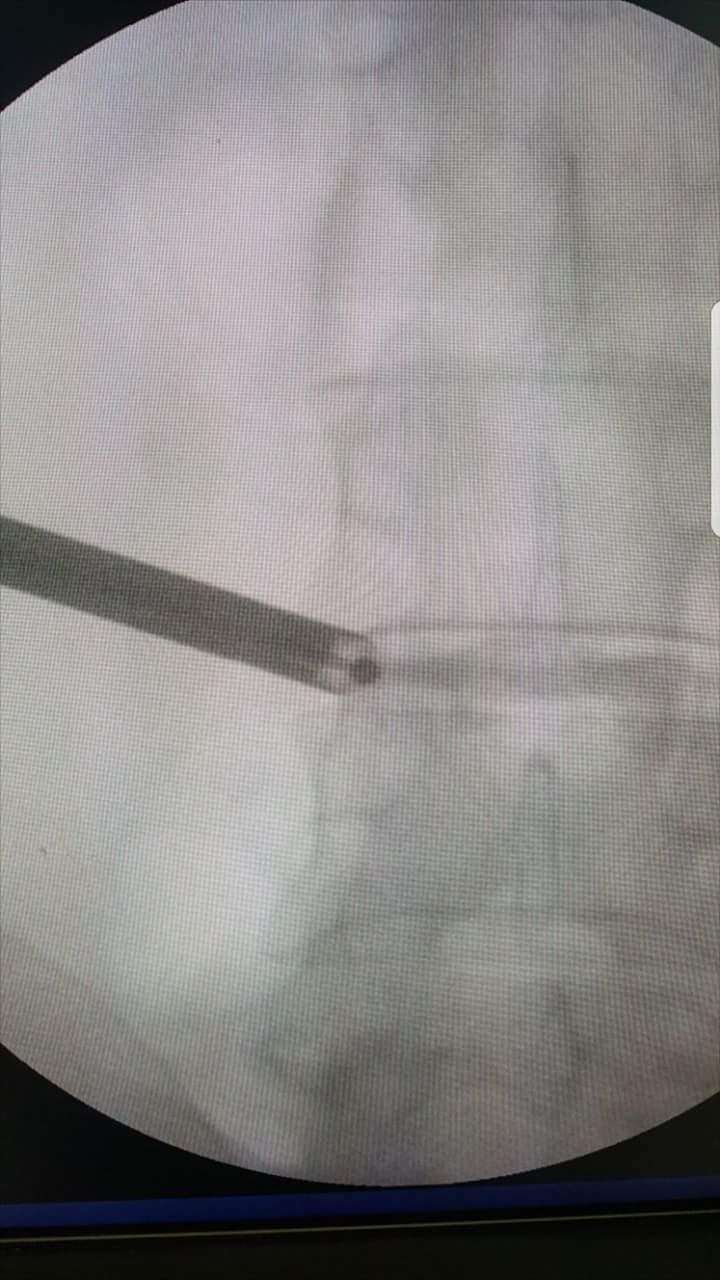

Endoscopic discectomy under Local Anaesthesia.

Big L5 S1 disc causing severe pain in left leg

Removed disc fragment in awake n aware anaesthesia.

Patient was watching the whole procedure at screen and was responding to commands.

Skin incision was just 6 mili meter

No stitch required at end of procedure

Biggest advantage of this procedure is that since patient is awake he will not allow surgeon to injure any neural structure

Safe Spine Surgery

Dr. I P AGRAWAL, SHALBY HOSPITAL, JAIPUR